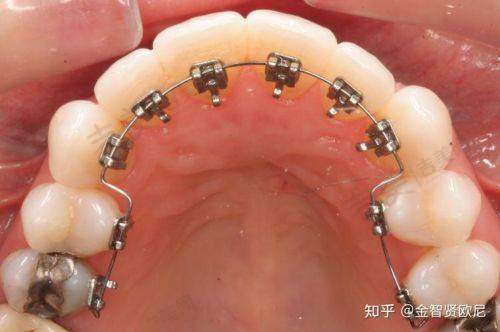

各领域优势:在牙齿种植方面,门诊部拥有精良的技术和经验多的医生,能够为患者提供多种种植方案,确保种植成效的稳定性和美观性。牙齿美白项目采用安心有效的美白技术,能够快速改善牙齿颜色,让患者拥有洁白亮丽的牙齿。牙齿矫正科室运用精良的矫正技术和设备,根据患者的具体情况制定个性化的矫正方案,帮助患者拥有整齐的牙齿。口腔美学修复和口腔综合治疗科室也为患者提供了全方面的口腔诊疗服务。

特色项目优势:武汉左岭博牙口腔门诊部的特色项目众多。牙齿种植项目采用精良的种植技术和优质的种植体材料,医生会根据患者的口腔情况和需求,制定个性化的种植方案,确保种植后的牙齿稳定性好、咀嚼功能强,与自然牙齿无异。牙齿美白项目运用安心有效的美白技术,能够在不损伤牙齿的前提下,快速改善牙齿颜色,让患者拥有洁白的牙齿。牙齿矫正项目拥有多种矫正方式可供选择,如传统金属矫正、隐形矫正等,医生会根据患者的牙齿畸形程度和个人需求,选择更适合的矫正方案,帮助患者实现牙齿整齐美观的愿望。口腔美学修复项目注重牙齿的美观和功能的结合,通过修复技术改善牙齿的形态和色泽,提升患者的口腔美观度。口腔综合治疗项目则为患者提供了全方面的口腔疾病治疗服务,包括龋齿治疗、牙周病治疗等,确保患者的口腔健康。